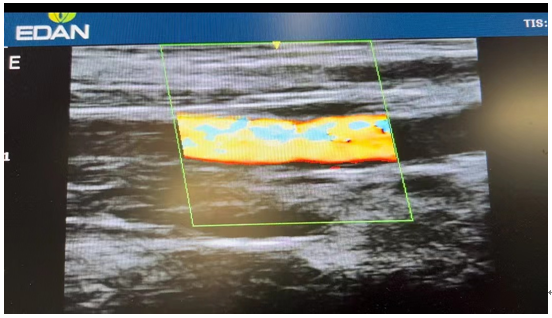

手术很成功,术后复查超声示近心端桡动脉明显扩张,内瘘血流信号良好,可扪及血管震颤明显,一个闭塞了七年之久的动静脉内瘘又恢复了往日的功能。经过医生护士的精心治疗,郭大叔满意地出院了。“感谢湘南学院附属医院,多亏了你们医生的精湛技术和护士的细心照顾,我又可以用内瘘做血透了。”临行前,郭大叔激动地向医务人员表达着感激。